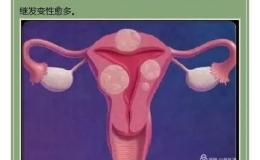

“钥匙孔”里终结子宫肌瘤——东方集团寿县济民医院成功开展首例妇科腹腔镜手术

【综合新闻】 2018-12-21 16:08:00 188 次 -